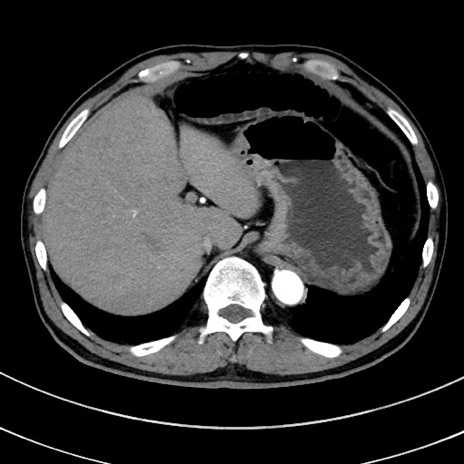

症例8(横断像)

【症例】 60歳代男性

【主訴】 黒色吐物

【現病歴】 4日前から嘔気自覚、2日前の朝食後にも嘔気あり、自分で手で嘔吐反射起こし嘔吐したところ血が混ざっていたため受診。

【既往歴】 5年前汎発性腹膜炎を伴う急性虫垂炎で手術、高血圧、前立腺肥大症、高脂血症

【身体所見】 腹部正中に手術癩痕あり 腹部平坦・軟圧痛なし膨満感あり

【データ】WBC 8400、CRP 4.54